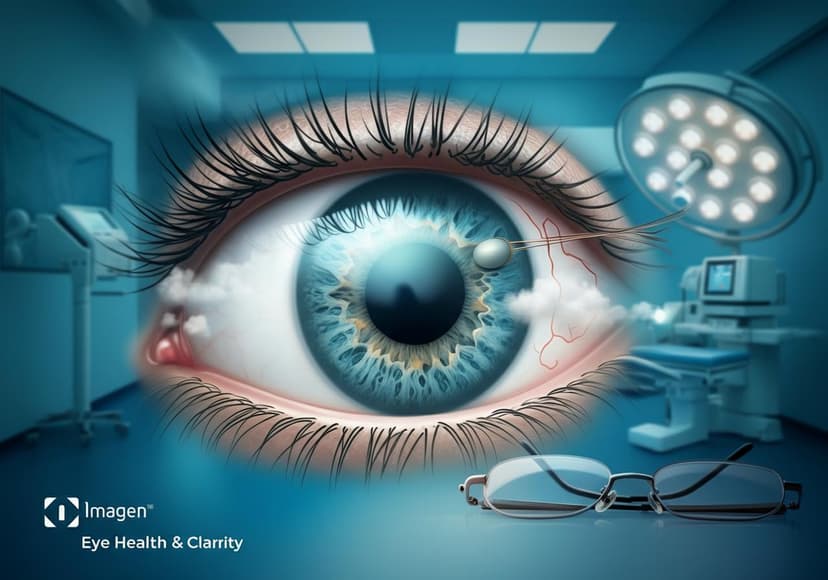

Cataracts Symptoms And Treatment

Eye clinics offer comprehensive care. Early detection and treatment improve vision and prevent severe eye damage.